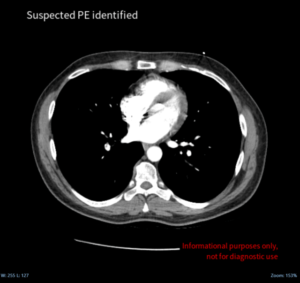

In addition to securing a CE mark in the EU, CINA CHEST has also received 510(k) clearance from the Food and Drug Administration (FDA) for its automatic detection and triage capabilities for both pulmonary embolism (PE) and aortic dissection from computed tomography (CT)-scan imaging.